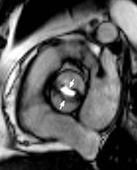

可用於心臟病、心肌病、心包腫瘤、心包積液以及附壁血栓、內膜片的剝離等的診斷。

MRA目前的臨床適應證正在日益擴大,近年來除用於顱頸部頸動脈和椎動脈疾病(梗阻與狹窄等)的檢查,顱內血管畸形,血管閉塞,動脈瘤,動靜脈等的檢查;也用於肝移植手術前肝臟血管系統的評估,腎動脈狹窄,以及周圍血管疾病的檢查等。心臟大血管的套用方面MRA除用於觀察心臟大血管的形態和能外,對冠狀動脈的顯示也已基本成功,對冠狀動脈主要分支的狹窄阻塞的診斷,檢查術後是否通暢的監測以及肺動脈栓塞的診斷等都有較大的套用價值。